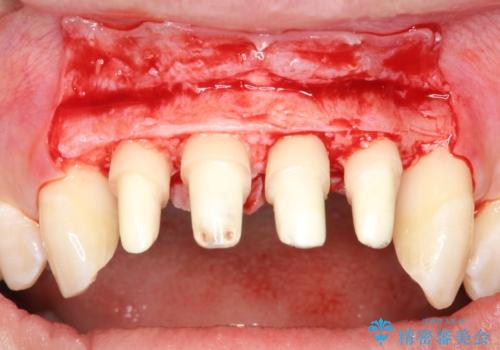

- 以前に前歯を折れた時、コンポジットレジンで修復したが、変色してきたことを主訴に来院されました。

今回は、セラミッククラウンによる修復を希望され、治療を行っています。

- 天然歯を削ります